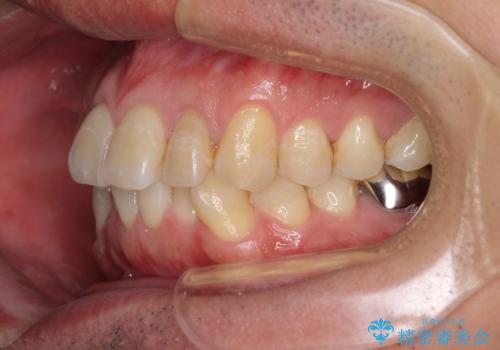

前歯のデコボコと下顎の八重歯 インビザラインによる矯正治療

- 前歯のデコボコや八重歯を気にして来院された患者様です。

インビザラインを用いて、歯列を整えることとしました。

下顎前歯は後戻りを起こしやすいため、舌側を細いワイヤーで固定し、マウスピース型リテーナーで保定を行うこととしました。